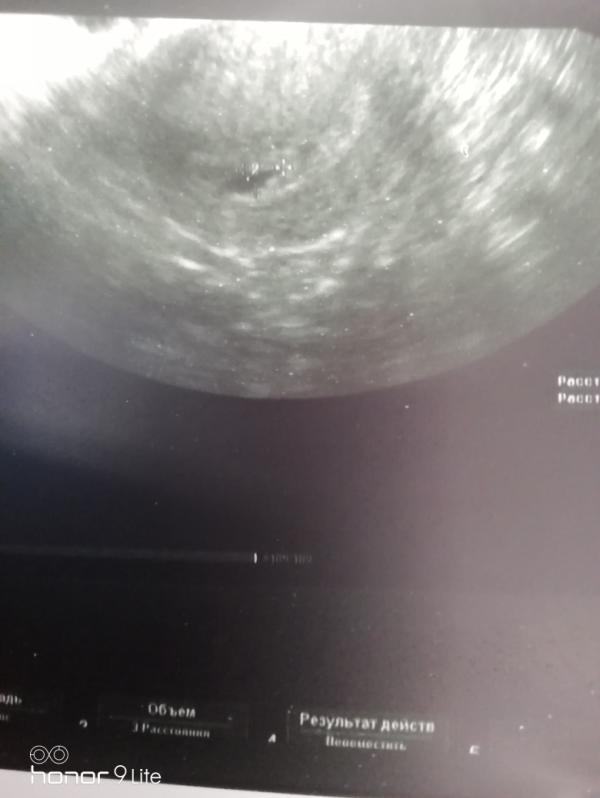

Итак мы были сегодня на первом УЗИ. Наш срок 3-4 недели, так что мы ещё пока очень маленькие😍😍😍

Но беременность маточная, а это самое главное. Так что будем расти дальше👶👶🙏🙏🙏

@plohih.natalia2016 да, ну по фото видно что ПЯ с эмбрионом)))